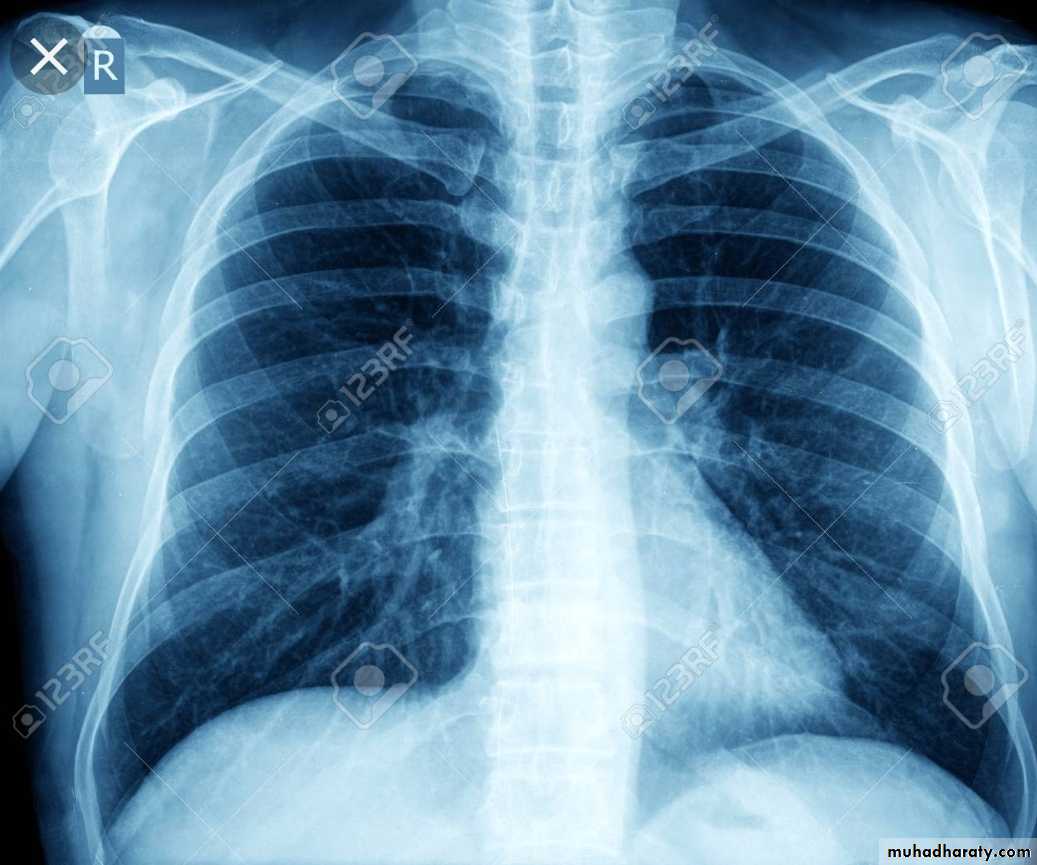

* Grossly: it forms a small sub pleural parenchymal lesion in the mid zone of the lung (Ghon focus) & spread to the hilar lymph nodes, both lesions are called Primary complex (Ghon complex).

Either occurs as a reinfection by mycobacterium TB or reactivation of primary infection when there is impairment in the immunity of the patient.Grossly: usually occurs at the apex of the lung with minimal lymph node involvement. There is marked damage in the lung parenchyma with cavity formation

X- ray,